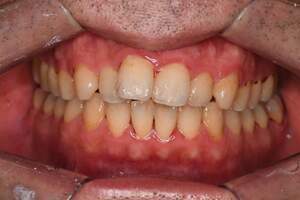

歯石除去

治療前

治療後

| 年齢 | 36歳・男性 |

| 主訴 | 歯石をとりたい |

| 治療内容 | 歯石除去 |

| 治療期間 | 30分 |

| 費用 | 約2,000円 |

| リスク・副作用 | ・歯ぐきの炎症が強いと歯石を取る際に出血することがあります。 ・処置後に歯がしみることがあります。 ・歯と歯の間に隙間ができるので、息が漏れ発音しにくいと感じることがあります。 ・歯ぐきの炎症が軽減すると歯ぐきが引き締まり、歯が長く見えることがあります。 |